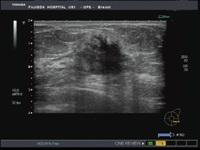

中央の黒い不整な乳腺組織を発見